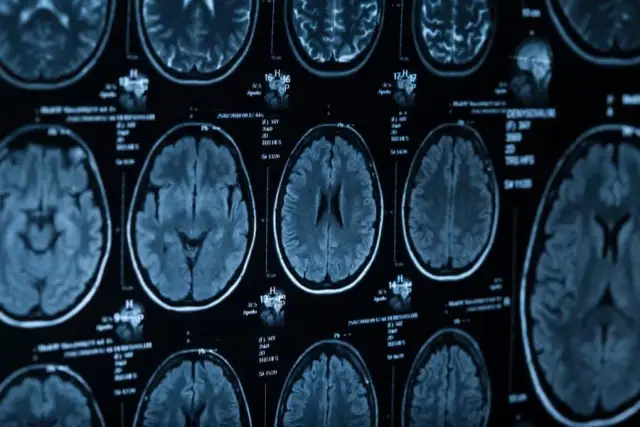

Kategoria Neurologia - Strona 2